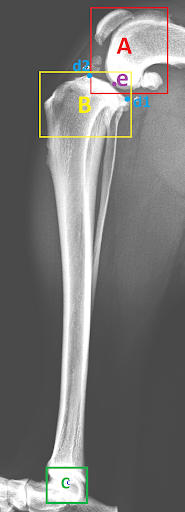

The dataset used for training was collected from various veterinary clinics, as none is available in the public domain, and the objects of interests were manually annotated. The resolution of these images vary largely as they are collected from various sources, thus for the sake of uniformity the images are all scaled to fit the same dimensions. The first part of this project was to develop a lightweight radiograph image sorting algorithm reported in [8]. The images chosen for the task described in this manuscript were all classified to be lateral lower body images by that sorting algorithm. Examples of manual annotations of objects of interests are given in Fig. 4: here regions A, B and C identify the joints while the point ’e’ identifies the centre of Talus and regions d1 and d2 identify the points that form the MTPL.

Most of the source dataset of over a thousand unique knee radiographs were distorted, had poor patient positioning, or were otherwise unfit for annotating. 250 of the original images were of sufficient quality to contribute to this effort. These images were set to have 6 different classes for training purposes, as mentioned and shown in Fig. 4. These were then trained using YOLOv3 [10] and the results of the predicted annotations are shown in Table I. From these predictions the centroids were extracted, which is then used to plot the FTL and MTPL. Then using the method mentioned in Section II, TPA is calculated. Examples of images, the region of interests detection and their respective TPA determination is shown in Fig. 6 and Table I: